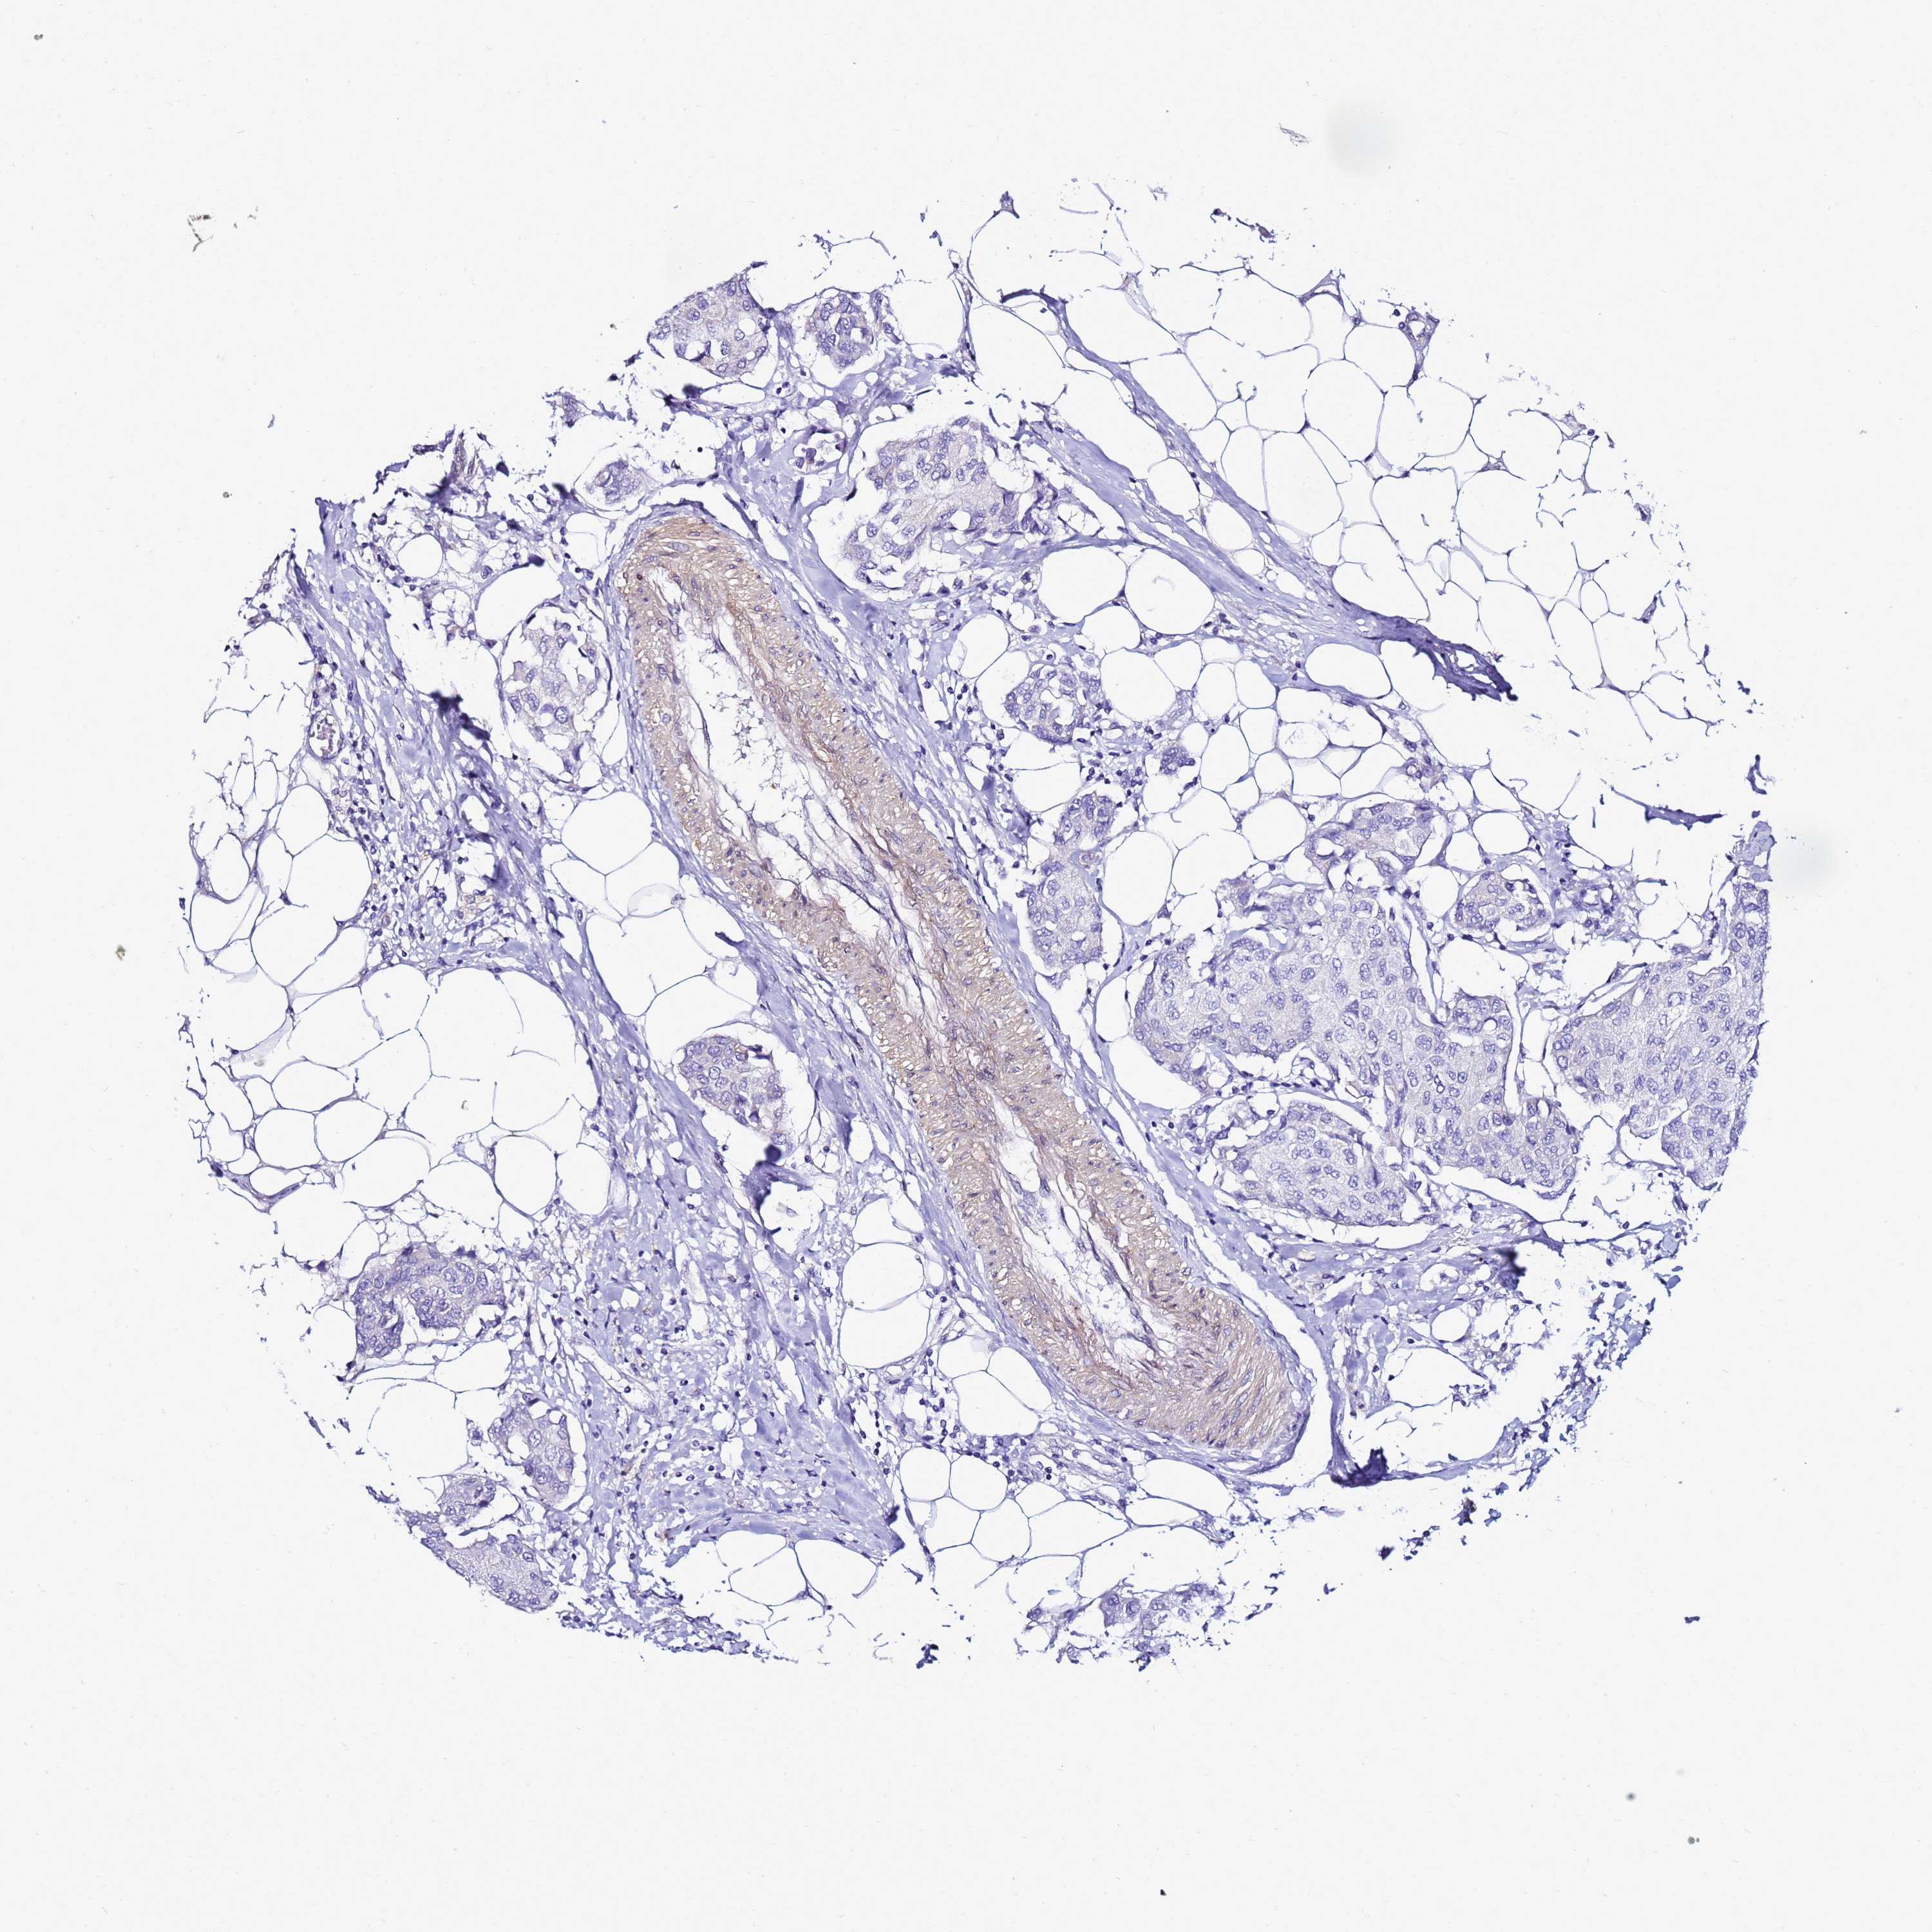

BRCA TCGA BRCA VALIDATION PROTEIN EXPRESSION